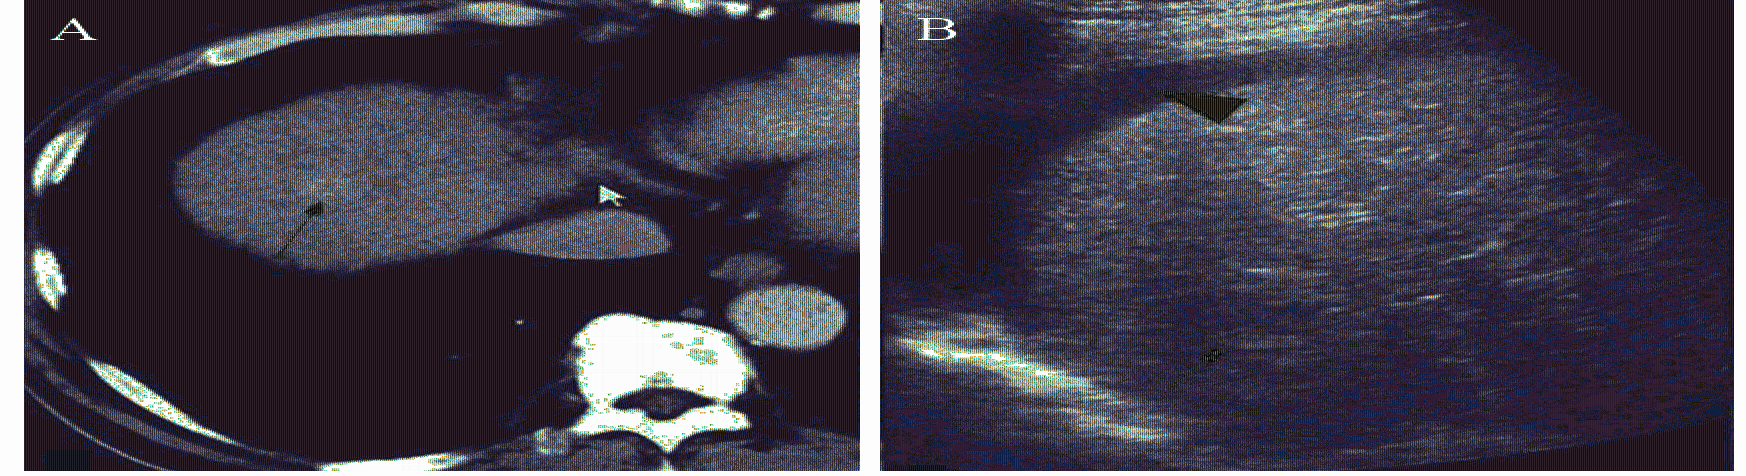

人工腹水建立的方法参照Seldinger穿刺技术[6, 7, 8]并进行改进:患者取仰卧位,常规消毒铺巾,取第7~8肋间隙与右腋前线交点为穿刺点,2%利多卡因局麻穿刺点至腹膜,超声实时引导下,用5-F动脉鞘穿刺套件(Terumo corporation,Japan)21G穿刺针穿刺入肝与腹膜之间的间隙后退出针芯,在超声实时引导下沿套管将导丝置入右侧膈顶部,将5-F动脉鞘管沿导丝方向置入右侧膈顶部,经动脉鞘滴注5%葡萄糖溶液750~1 500 ml[9],见图 1。实时超声监测腹腔内人工腹水厚度,直到肝脏上界下移,肝脏与膈肌分离,膈顶部肿瘤位置显示清楚,穿刺路径完全显露,视为人工腹水建立成功,见图 2。

| 图1 建立人工腹水的方法 Figure 1 Establishment methods of artificial ascites |

| A: ultrasound was unable to display some lesions in the hepatic dome before artificial ascites; B: after the establishment of artificial ascites, the lesions could be fully displayed by ultrasound. C: after the establishment of artificial ascites, hepatocellular carcinoma in the hepatic dome could be fully displayed by ultrasound 图2 建立人工腹水效果图 Figure 2 Schematic diagram of establishment process of artificial ascites |

患者成功建立人工腹水后,见图 3,应用RF-2000TM射频治疗仪及集束电极针(Radio Therapeutics Corp,USA),在LOGIQ E9超声诊断仪(General Electric Company,USA)实时引导下将射频针穿刺入病灶底部,采用多点逐层布针方式,每层5 mm,逐层打开治疗伞进行RFA治疗,要求消融范围覆盖整个肿瘤,并且超出肿瘤边缘5~10 mm。射频治疗仪输出功率由30 W逐步增加至80 W直至RFA治疗完全,以防止针道转移,最后拔针前注意针道烧灼,穿刺点止血。

| A: The lesions were located in the diaphragm dome(fine red arrow) before radiofrequency ablation(RFA) showed by CT; B: After the establishment of artificial ascites(thick red arrow), the lesions in the back diaphragm dome could be fully displayed by ultrasound(fine red arrow);C: Percutaneous ultrasound-guided RFA with artificial ascites (thick red arrow) for hepatocellular carcinoma in the hepatic dome(fine red arrow);D: After RFA, tumor (thin red arrow) was completely ablated, and concurrent reactive pleural effusion (thick blue arrows) was showed by CT 图3 人工腹水辅助射频消融治疗膈顶部原发性肝癌前、治疗中及治疗后示意图 Figure 3 Schematic diagram of hepatocellular carcinoma in hepatic dome before, during and after artificial ascites with RFA treatment |

所有22例患者参照Seldinger穿刺方法均置管成功,5%葡萄糖溶液的注入量为(943.2±187.9) ml。但仅19例(19/22,86.4%)患者22个病灶(22/25,88.0%)成功在膈下形成局限性的人工腹水,厚度(肝右叶顶部距膈肌的最大距离)为(3.4±1.3)mm。22个成功建立人工腹水的病灶中,13个由于肺气的遮挡常规超声不能显示完全病灶范围,9个穿刺路径被肺气或肋骨阻挡,建立人工腹水后所有病灶位置及范围完全显示,并清晰显示穿刺路径。3例患者3个病灶(3/25,12.0%)注入5%葡萄糖溶液后未能在局部形成局限性的人工腹水,其中2例患者为HCC手术切除后复发病例,腹腔粘连严重,注入5%葡萄糖溶液后仍无法将肝脏与膈肌分离,1例为肿瘤位于肝Ⅷ段肝裸区内,注入5%葡萄糖溶液亦无法令肝脏与膈肌分离,故3例患者在无人工腹水辅助下行RFA治疗,术后一个月增强CT/MR随访复查病灶消融完全,但1例患者局部膈肌血供消失。其余19例患者22个病灶在人工腹水辅助下完成RFA治疗,治疗后一个月增强CT/MR随访复查均提示消融完全,膈肌血供正常。 2.2 人工腹水的安全性